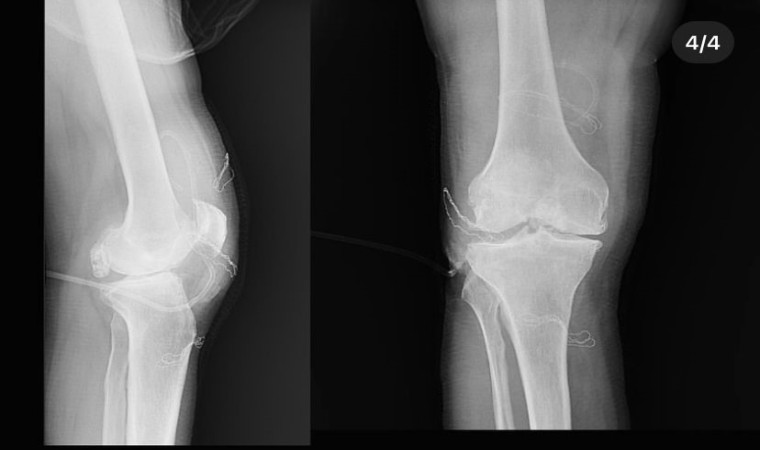

Diz ağrısı şikayeti ile geldiği Düzce Üniversitesi Tıp Fakültesi Hastanesi’nde ameliyata alınan hastanın dizlerinden toplam 41 adet multipl sinovial kondromatozisi çıkartıldı. Özellikle diz eklemi çevresinde görülmekle birlikte kalça, dirsek ve diğer eklemlerde de görülen, ufak parçalardan oluşan cisimler olarak tanımlanan eklem faresi, eklem çevresinde eklem sıvısı ya da sinoviyumda görülen kıkırdak ya da kemik parçalarıdır. Eklem farelerinin boyutları birkaç milimetreden birkaç santimetreye kadar çıkabiliyor.

Düzce Üniversitesi Tıp Fakültesi Hastanesi Ortopedi ve Travmatoloji Kliniği’nde başarılı geçen operasyonu; Doç. Dr. Zekeriya Okan Karaduman, Doç. Dr. Mehmet Arıcan ve Dr. Öğr. Üyesi Sönmez Sağlam gerçekleştirdi.